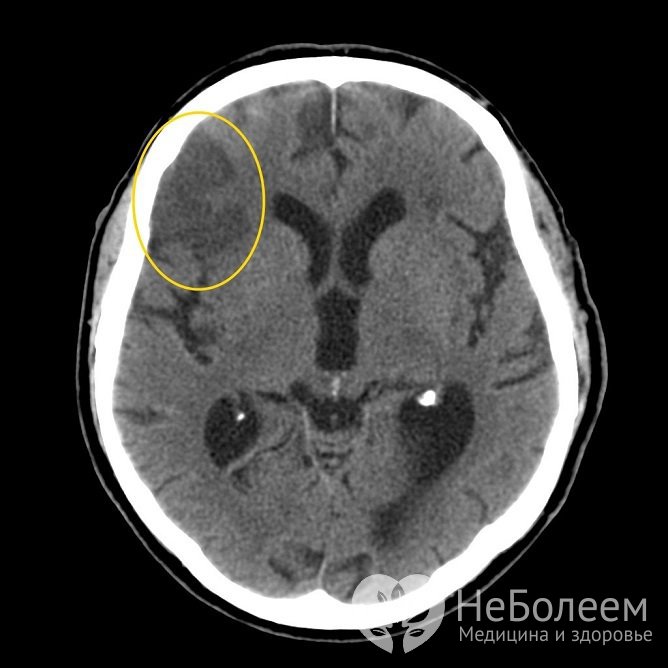

Ишемический инсульт на КТЛечение ишемического инсульта проводится по нескольким направлениям: